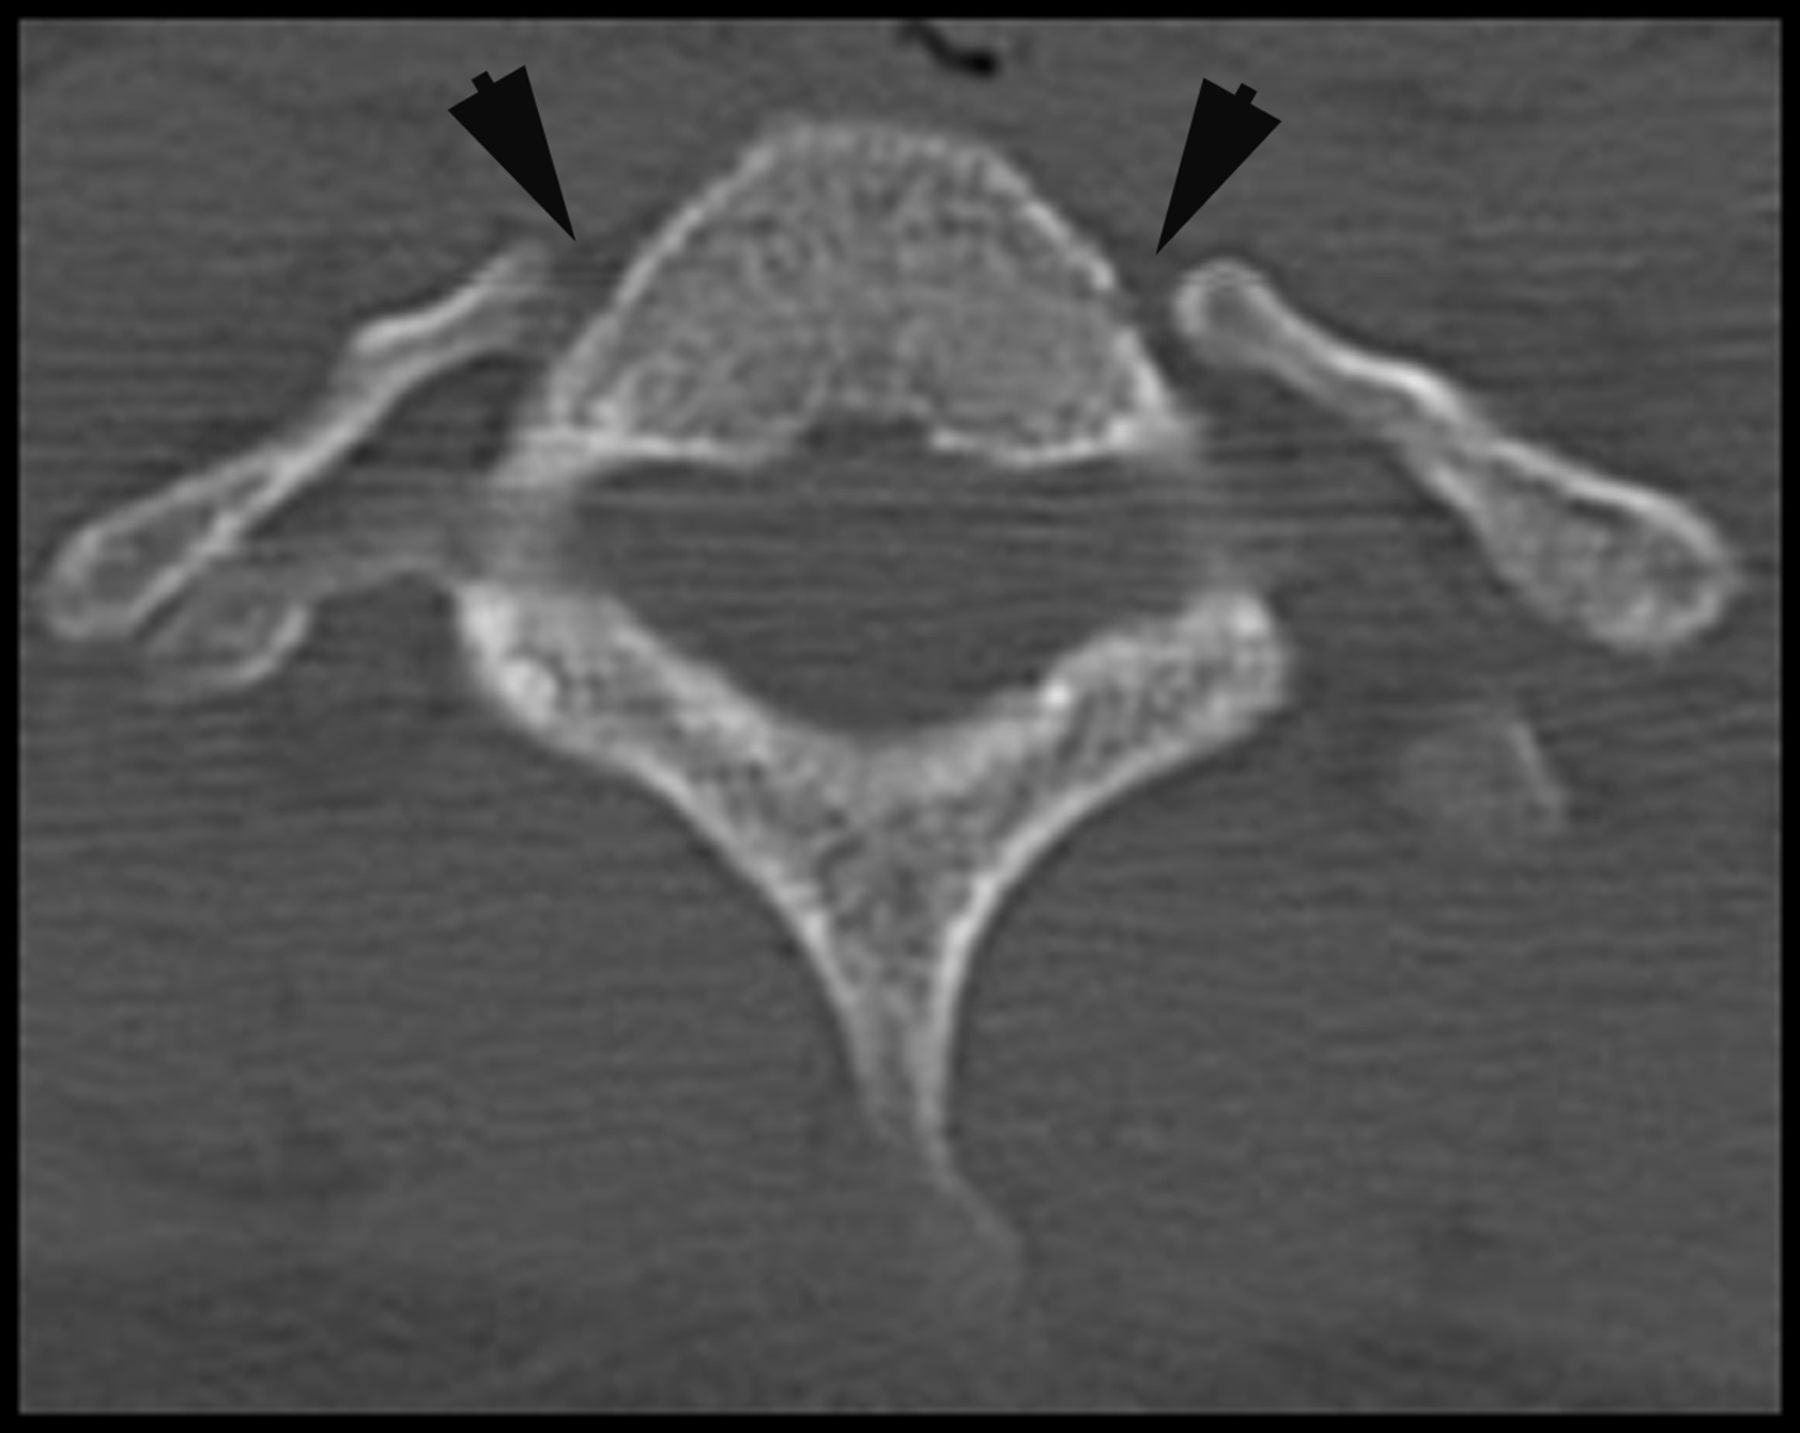

Any scan that the readers deemed to have a cervical rib was checked for accuracy by an expert reviewer with 23 years of subspecialty neuroradiology service. Figure 1 shows an example of bilateral processes that meet these criteria for cervical ribs. A separate data sheet was compiled containing all cross-sectional neuroradiology reports in the past decade, from May 31, 2001, to May 31, 2011, containing the words “cervical ribs.”

Axial CT image of bilateral cervical ribs.